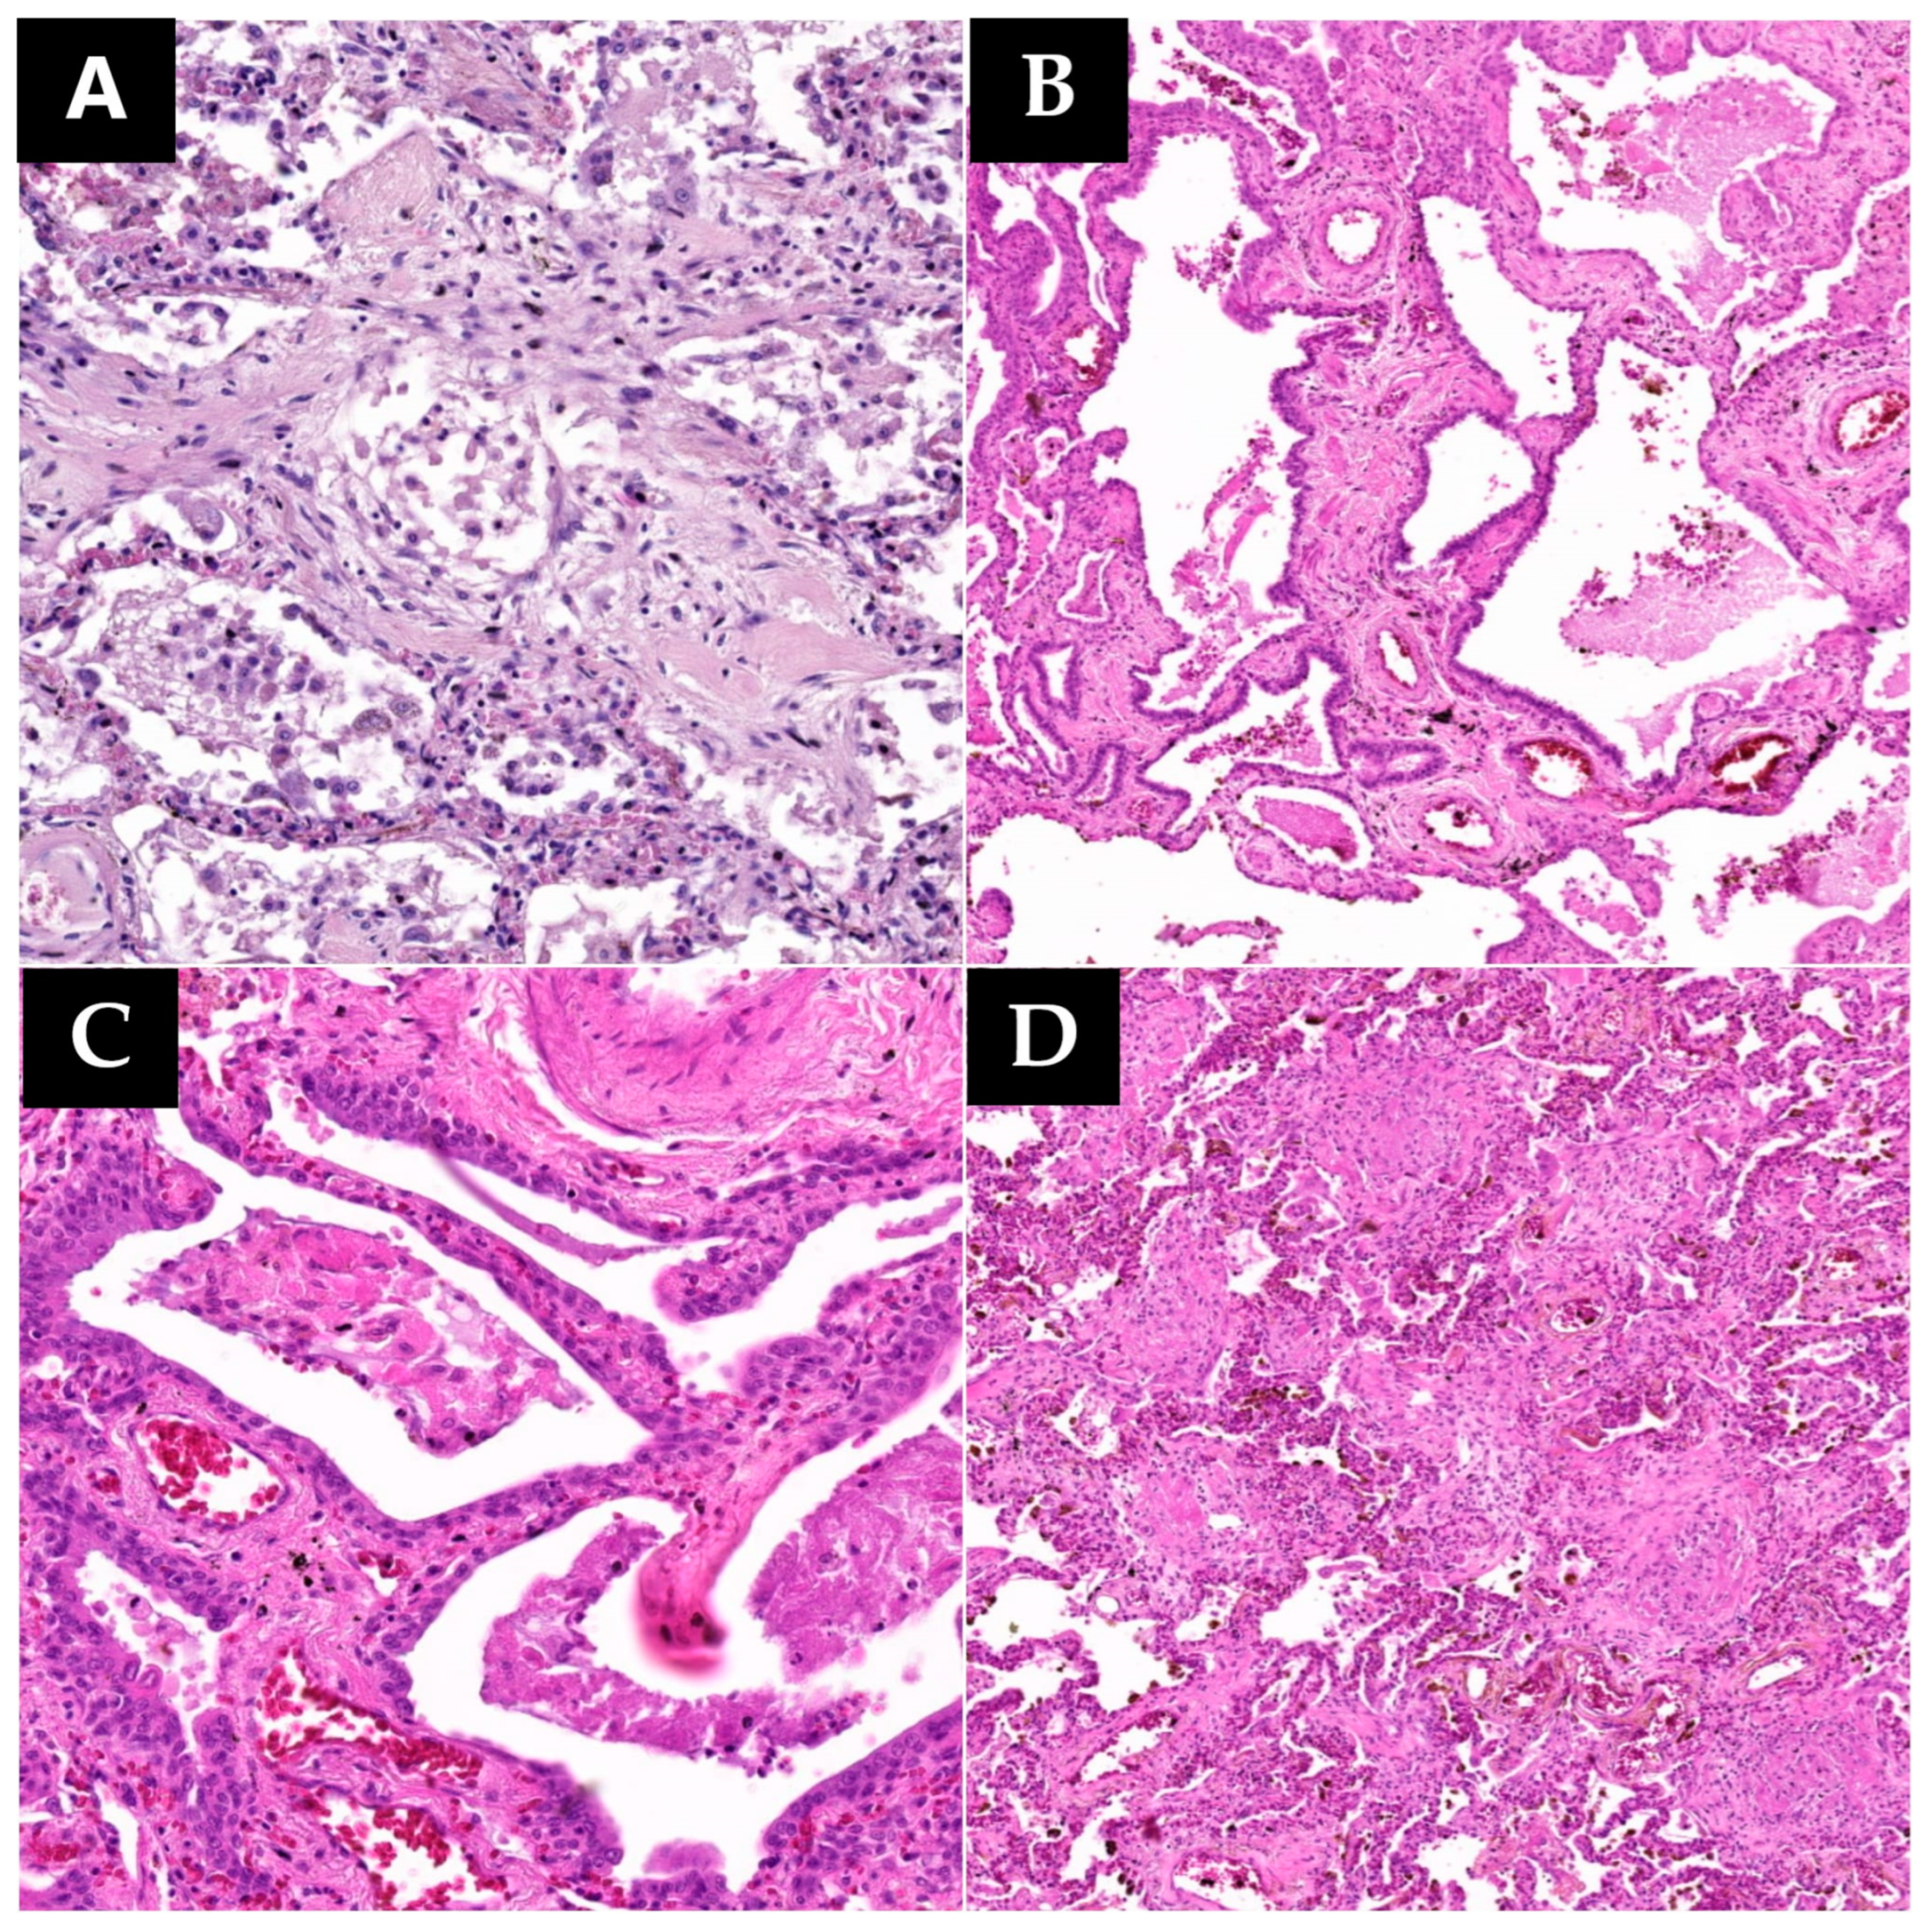

In specimens collected from 13 patients, histopathological examination revealed changes secondary to alveolar lesions, with the most common being type II pneumocyte hyperplasia. Among patients with suggestive histopathological changes in type II pneumocyte hyperplasia, 10 exhibited variable proportions of hyperplastic pneumocytes with cytopathic effects (

Figure 2). Cytopathic effects result from the invasion of a cell, typically by a cytopathic virus, leading to morphological, physiological, biological, and genetic alterations. Virally infected cells undergo shape and size changes, dysfunction of the cytoskeleton, and secondary nuclear changes and often display cytoplasmic or nuclear inclusions formed by newly formed virions or their structural proteins [

16].

In six collected specimens showing pneumocyte hyperplasia with viral cytopathic effects, altered cells occasionally fused to form syncytia, referred to as pneumocytic aggregates with giant cell-like formation or syncytial giant cell-like aggregates (

Figure 2). These can be easily mistaken for multinucleated giant cells of histiocytic origin. This was confirmed by CF7 and TTF1 positive immunostaining and CD68 negative immunostaining. Syncytium formation involves cell-to-cell fusion and is commonly observed in infectious processes. The ability of viruses to mediate membrane fusion for host cell invasion is employed for transmembrane transfer between infected donor cells and neighboring uninfected cells, facilitating local–regional expansion and potentially contributing to syncytium formation. The formation of syncytia is primarily mediated by specific interactions between viral fusion proteins and surface molecules or receptors expressed on adjacent uninfected cells [

17]. Giant-like cells in autopsy specimens exhibit wide aggregates with eosinophilic cytoplasm, abundant large nuclei, round-oval, irregular, homogeneous chromatin, predominantly peripheral nuclear disposition, visible nucleoli, disordered nuclear arrangement without a specific pattern, and occasional discernible boundaries between fused cells.

Another significant histopathological change within the spectrum of diffuse alveolar lesions is the formation of hyaline membranes, observed in nine cases. These membranes consist of dense, intensely eosinophilic, acellular bands on the inner surface of alveolar walls, composed of pneumocytic debris and fibrin (

Figure 2).

Addressing acute changes, vascular lesions, including microthromboses and vasculitic reaction, were observed in the current cases. Microthromboses, extensively discussed in the literature, underscore the need for anticoagulant treatment in severe COVID-19 pneumonia. Hence, this study emphasized the inclusion of tissue specimens from diverse pulmonary areas for effective vascular evaluation, covering broad lung fields. Vascular thrombi, of either small or large caliber, were observed in five cases (

Figure 2). In contrast, vasculitic reaction was noted in only three patients. Histologically, the vasculitic reaction did not manifest as classic leukocytoclastic vasculitis with secondary fibrinoid necrosis. Instead, it exhibited a lymphocytic nature, with lymphocytic groups penetrating the vascular wall from the adventitia toward the vascular endothelium (

Figure 2). Among these patients, only one presented both types of vascular lesions.

Histopathological examination revealed a series of hemodynamic changes, primarily characterized by pulmonary edema and diffuse alveolar hemorrhage. Accordingly, seven cases exhibited pulmonary edema, while eight cases showed diffuse alveolar hemorrhage. Among these, five patients presented both pulmonary edema and diffuse alveolar hemorrhage, and ten patients exhibited at least one form of these two conditions.